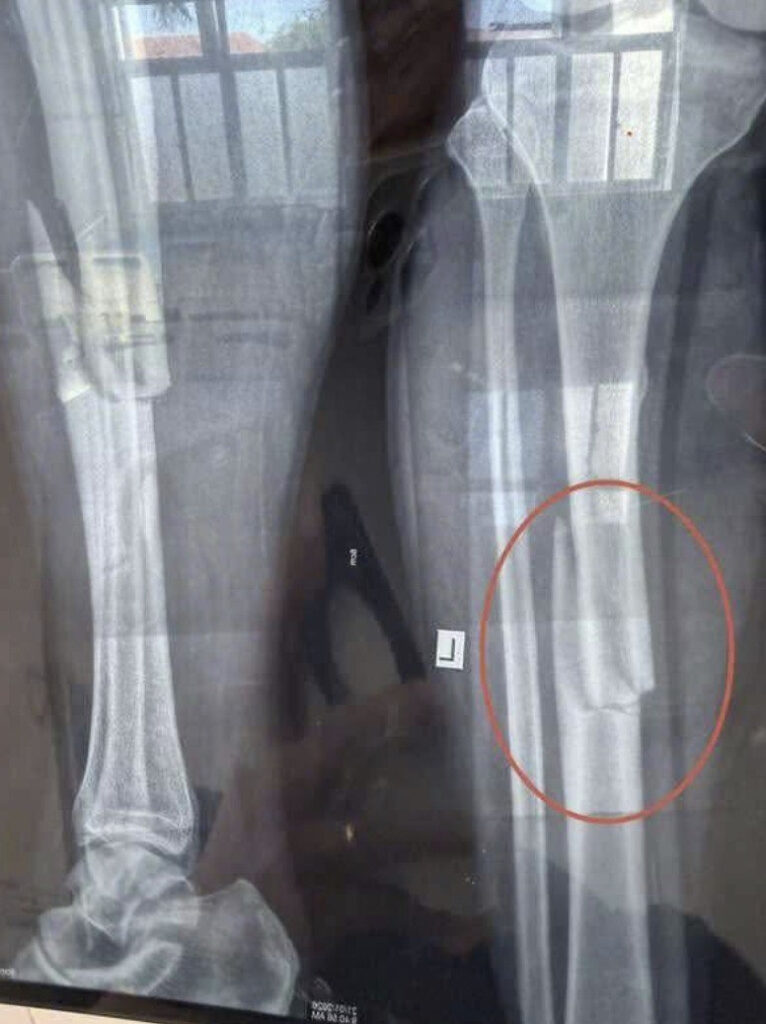

Tin Tức Vid – Hiên trường TNLĐ trong lúc làm việc Posted on Tháng 1 23, 2026Tháng 3 20, 2026 by m1med 23 Th1 Mọi người chú ý an toàn khi làm việc… m1med Chiếc xe merc bị cào xước và chiếc bill 116 triệu [VIDEO] Bị nhắc không được hút thuốc trên xe người đàn ông TĐVL luôn tài xế taxi